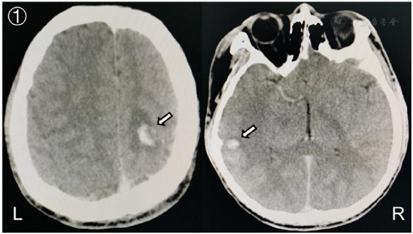

入院后给予脱水降颅压、低分子肝素桥接华法林抗凝、丙戊酸钠抗癫痫、床旁肢体康复等治疗措施,控制INR在2~3之间,患者意识逐步恢复清醒,认知功能未见明显障碍,头痛症状明显缓解,未见肢体抽搐等症状发作,右侧肢体功能明显改善,肌力恢复至5-级,复查头颅CT(2020年11月19日)提示:左侧额叶、右侧颞叶出血灶较前吸收减少(图3);头颅MRV(2021年12月5日):右侧横窦纤细,乙状窦部分显示不清,上矢状窦管壁毛糙、粗细不均,对比前片有所缓解(图4)。